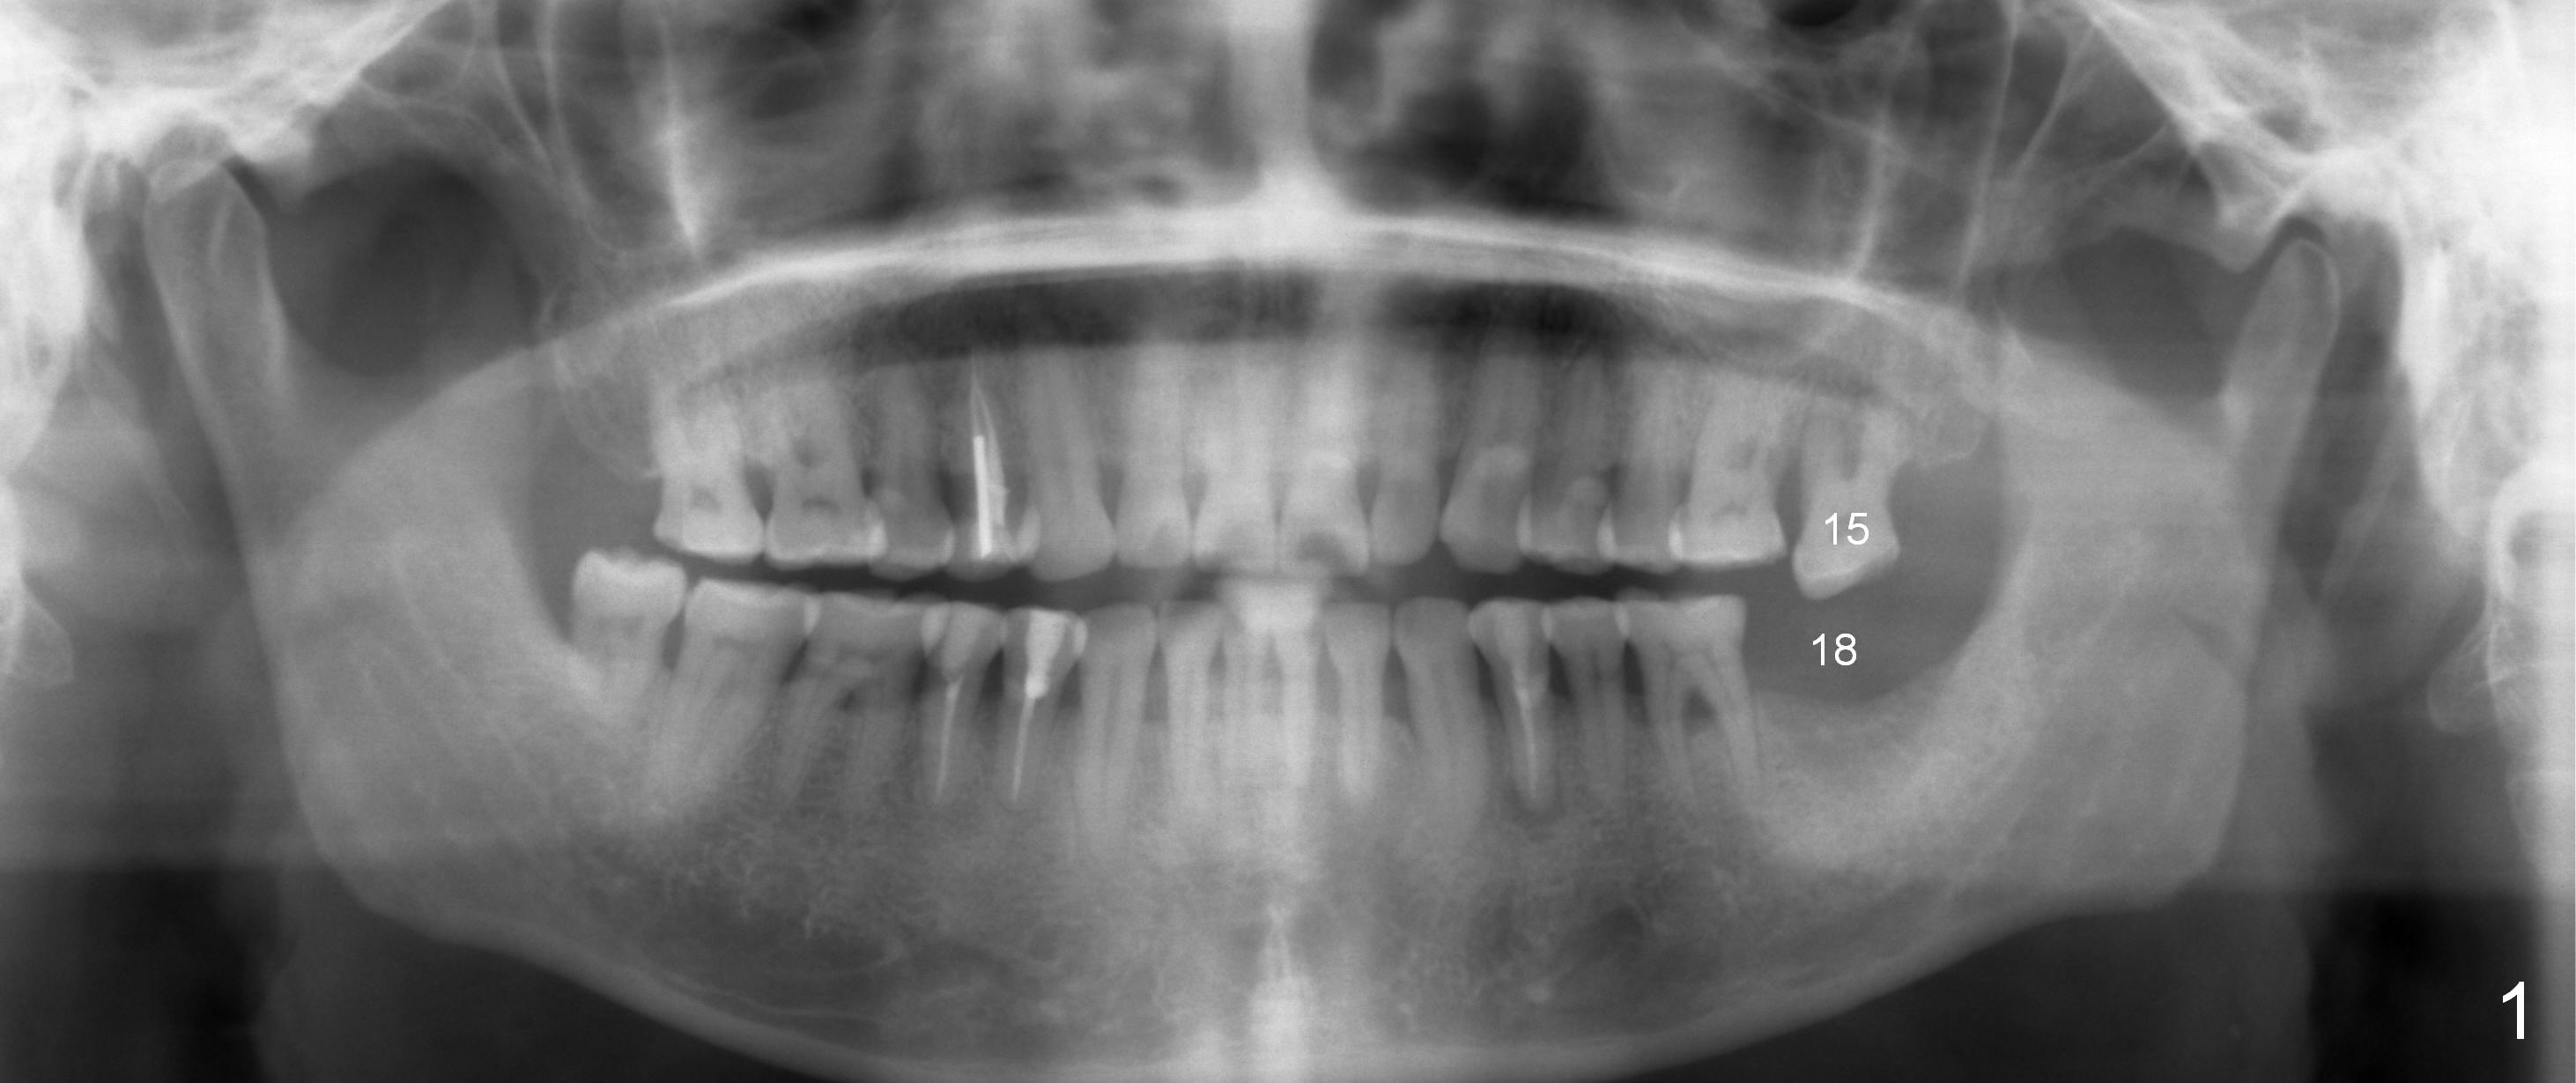

A 53-year-old man (ZB) has history of chronic periodontitis and bruxism. The tooth #18 has been extracted for a few years, while the tooth #15 is going to (Fig.1). Bone height for #15 immediate implant is not a problem (Fig.2-4; green line in Fig.2: sinus floor). After extraction (Fig.5 )socket to be treated with Clindamycin), use starter drill and a 2 mm pilot drill with stopper at 10 mm (Fig.6) on the crest of the septum (Fig.5 S). PA is taken with a parallel pin. Adjust the length accordingly. Subsequent osteotomy will be carried out with drills with stopper at 50 RPM. In brief, the implant does not need to be large. It should be placed as deep as possible (1-2 mm subcrestal mesially and/or distally), since the vertical height in the posterior region is limited. The margin of a cemented abutment is to be slightly subgingival. Use an immediate provisional to close socket gap, while to keep abutment margin from the gingiva. Use Collagen dressing before and after bone graft.